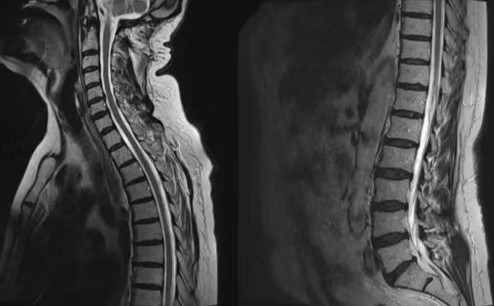

苏灿恍然大悟,茅塞顿开,马上安排了腰穿检查。检查结果提示压力的确小于60mmH2O。随后,苏灿请神经外科医生调整分流装置压力。

数天后,患者的症状缓解了。再次复查脊髓MRI时,已经看不见虫蚀样的血管流空影了(见下图)。

本章节改编自Neuroradiology 2017年的一则病例报告:Craniospinal Fluid Hypotension mimicking arteriovenous fistula onspinal MRI.